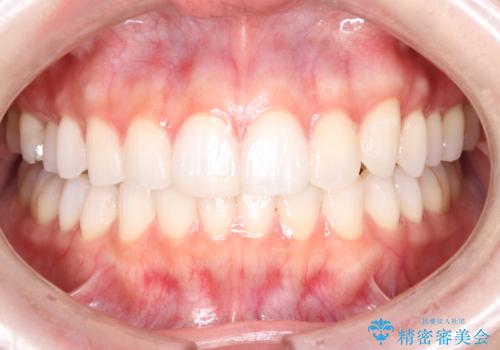

歯の中心のズレを解消し、より美しい口元へ